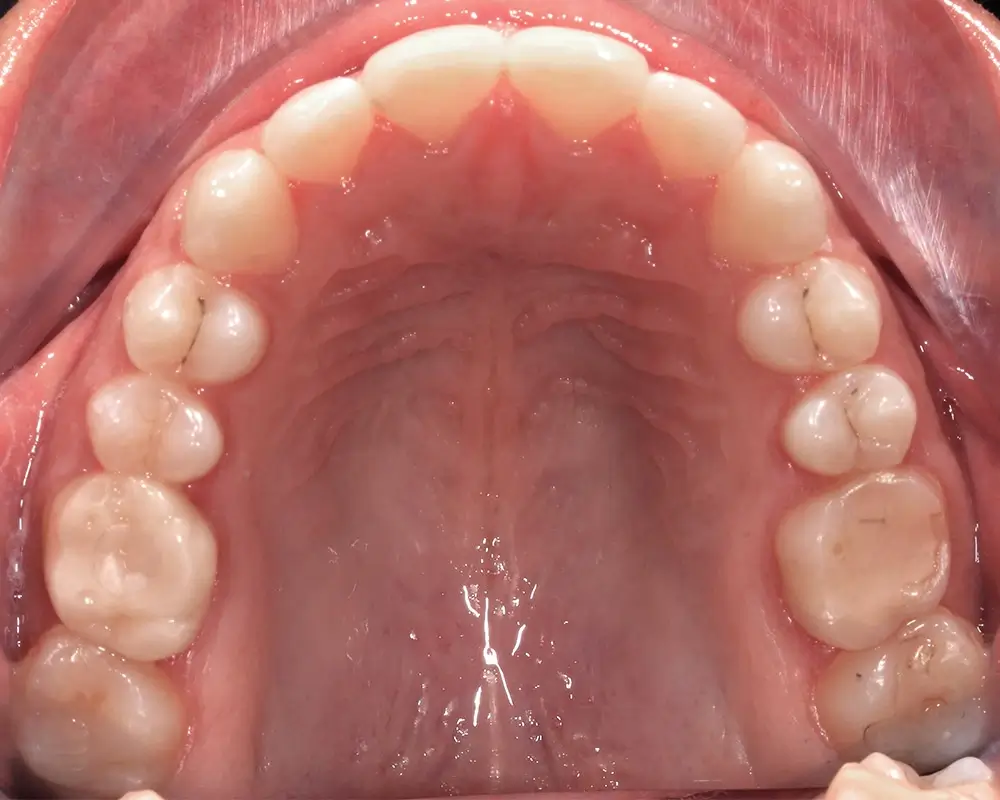

Открытый прикус - Кейс 5

Эффективность устранения дефекта прикуса посредством элайнеров FlexiLigner.

Результаты лечения